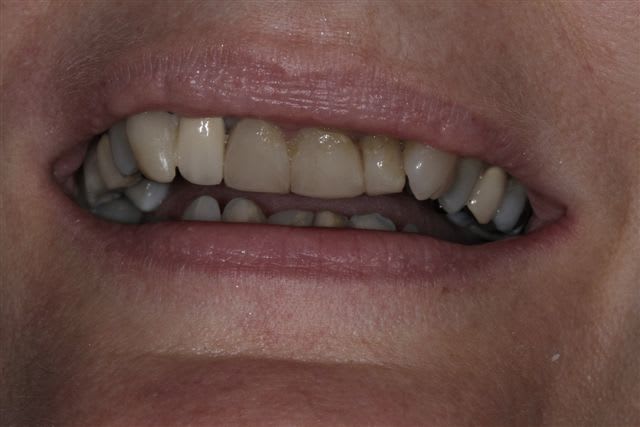

Vu les axes actuels des antérieures, soit tu gardes la même forme et les mêmes axes et tu auras de dents assorties mais pas vriament plus esthétiques. Sinon c'est ortho et la totale. Si tu changes la forme sans amélioration de l'esthétique ce sera l'echec mécanique assuré.

Je suis assez d'accord avec Ceramik, ce qui me saute aux yeux,outre l'esthétique bien sur, ce sont les courbes occlusales de la patiente, notamment secteur 2 et 3 en postérieurs(26 ne semble pas en occlusion, et 27 sur une pointe).

Le secteur antérieur doit donc supporter pas mal de contraintes... d'autant plus que le guide incisif semble assez fermé.

Perso, je ne toucherai à rien en antérieur,( d'autant plus avec du tout céram) tant que les courbes postérieures ne sont pas rétablies.

pour moi, réhabilitation globale.

Paro ++

refaire les courbes occlusales

en antérieur, faire un compromis pour légèrement corriger la classe 2.

à mon avis, plus de 4000 euros.